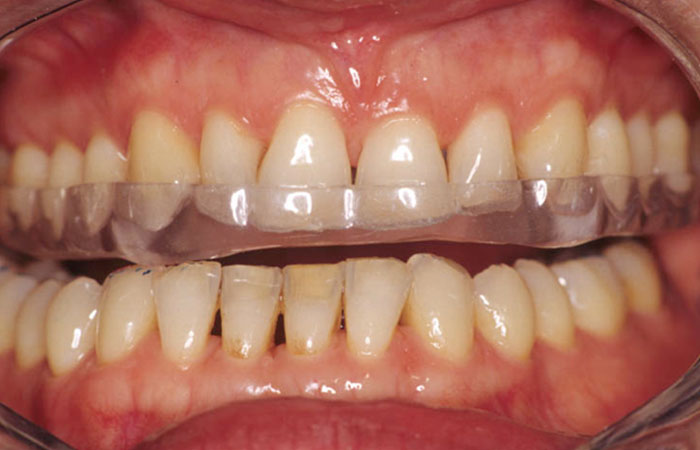

Bruxisme et usure dentaire